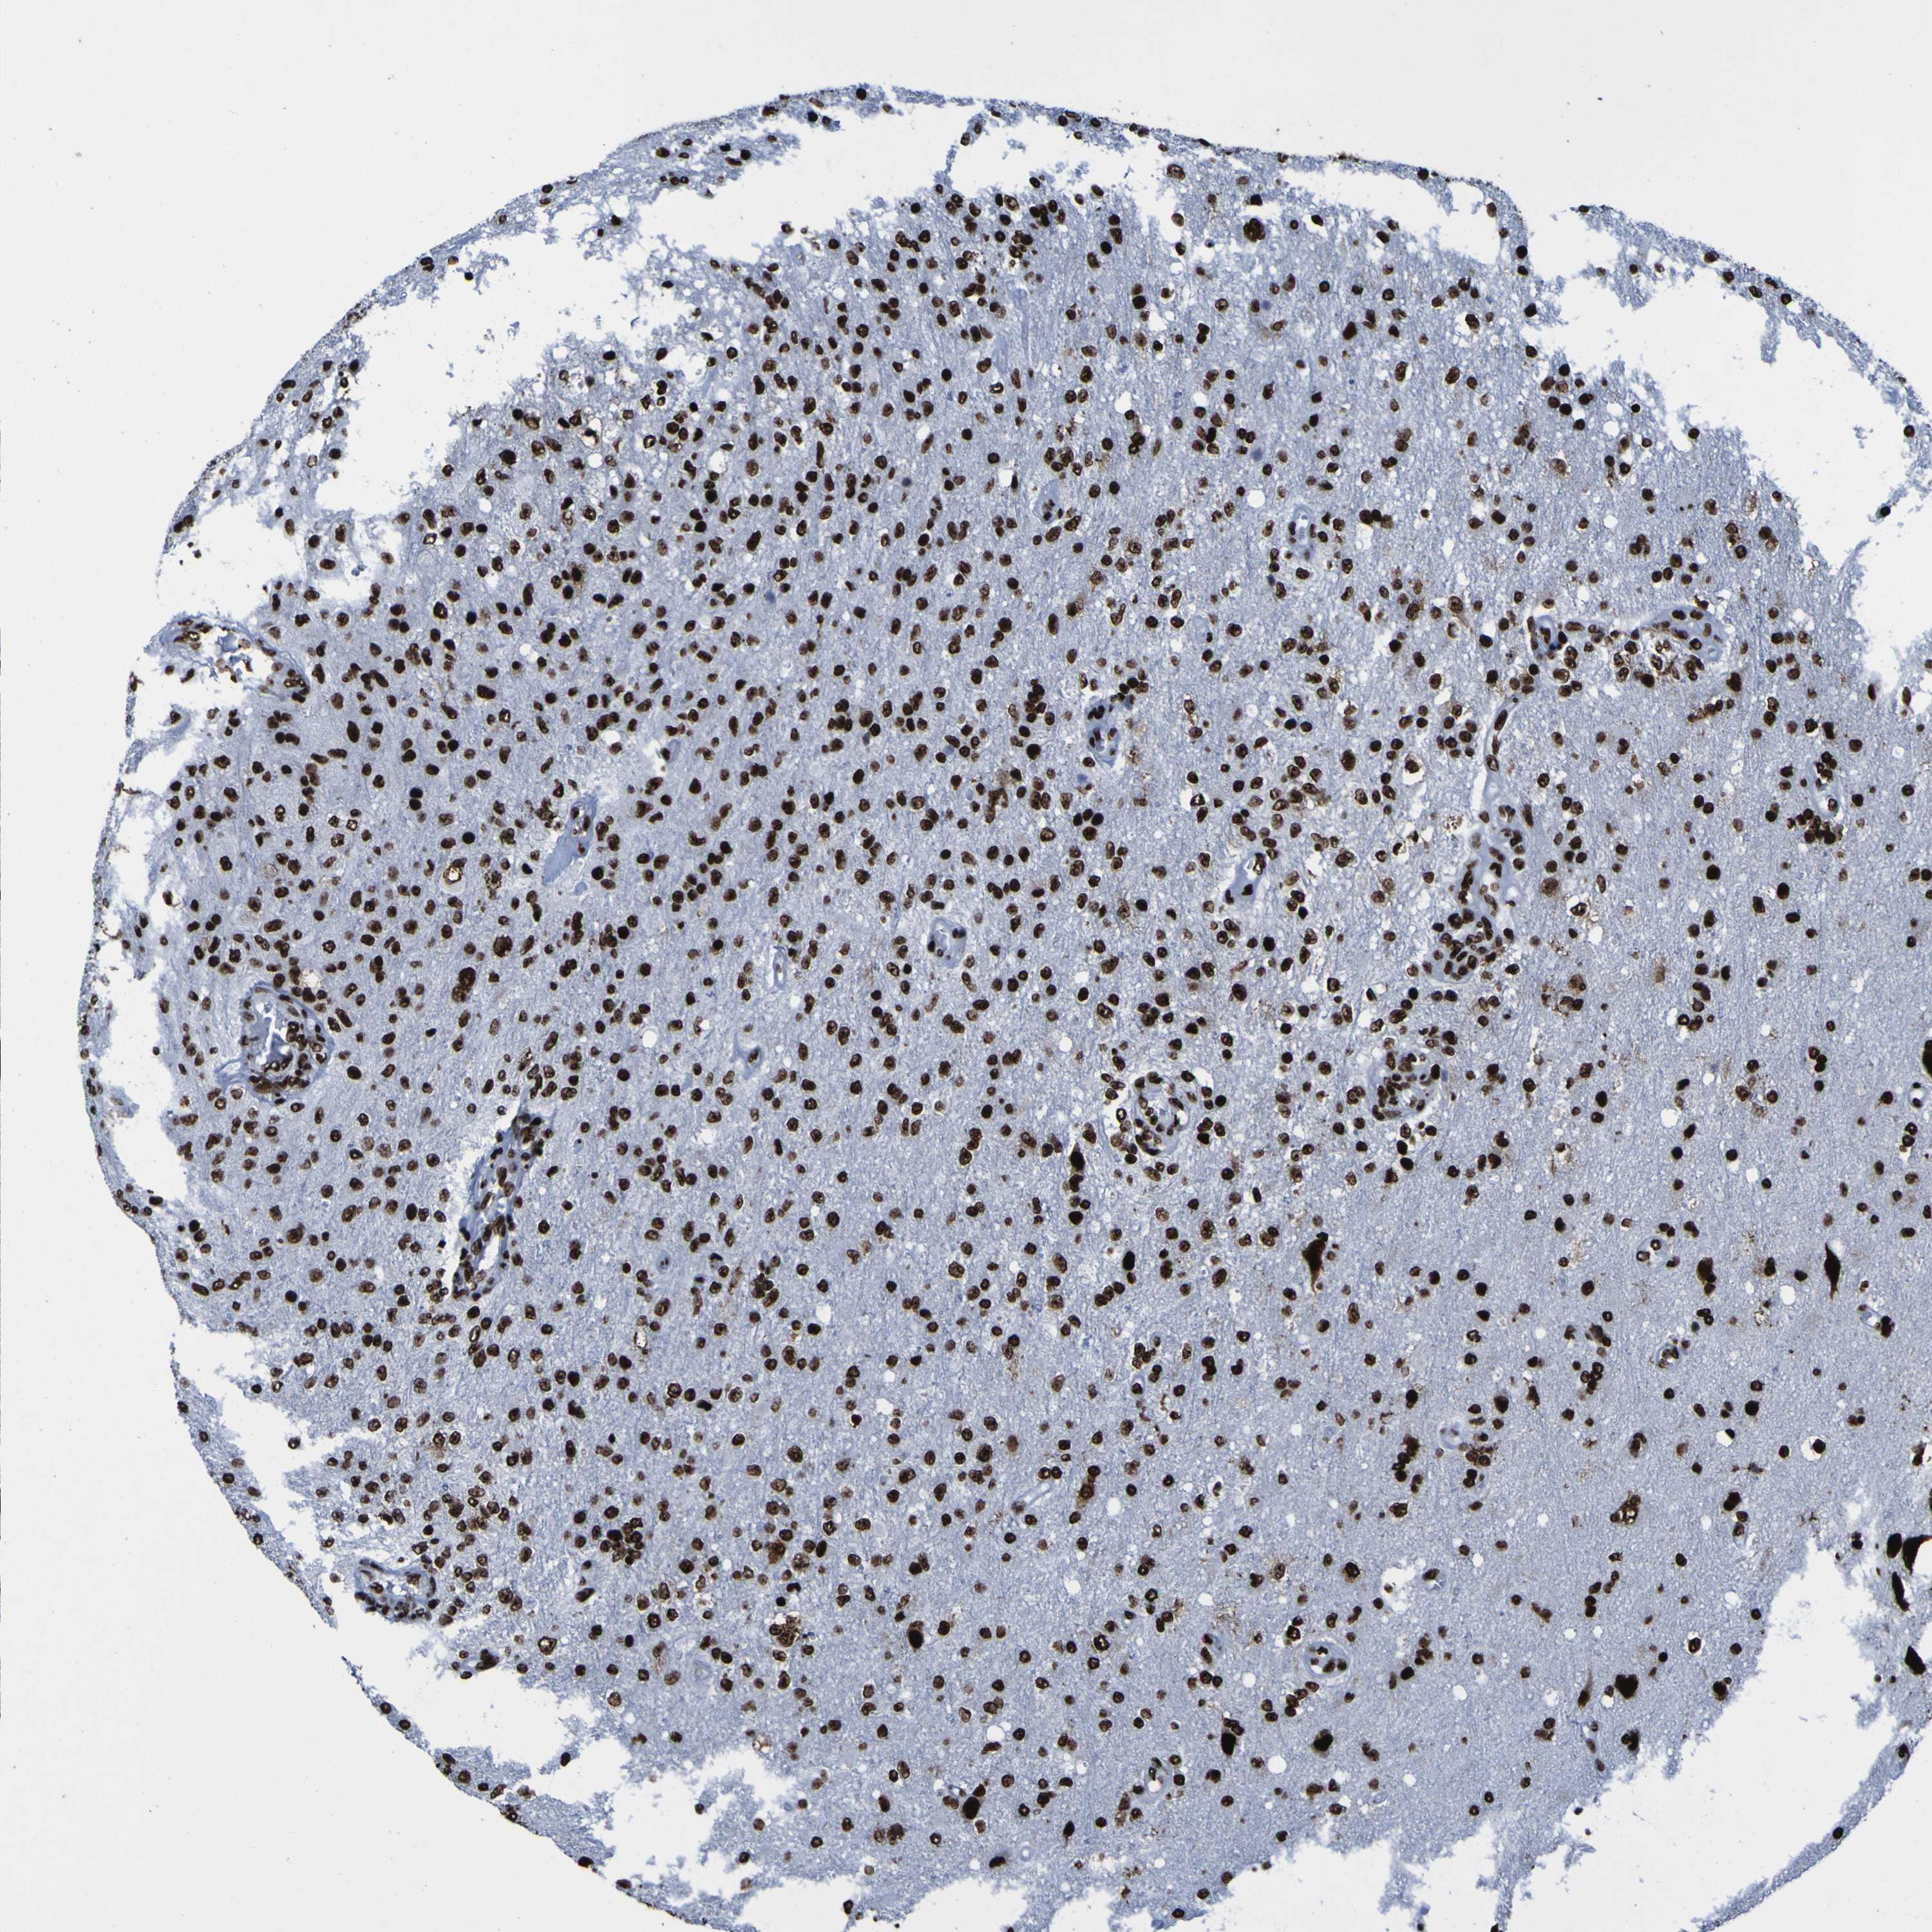

GLIOMA - Protein expressioni

A mouse-over function shows sample information and annotation data. Click on an image to view it in a full screen mode. Samples can be filtered based on level of antibody staining by selecting one or several of the following categories: high, medium, low and not detected. The assay and annotation is described here.

Note that samples used for immunohistochemistry by the Human Protein Atlas do not correspond to samples in the TCGA dataset.

Antibody stainingi

Antibody staining in the annotated cell types in the current human tissue is reported as not detected, low, medium, or high, based on conventional immunohistochemistry profiling in selected tissues. This score is based on the combination of the staining intensity and fraction of stained cells.

Each image is clickable and will lead to virtual microscopy that enables deeper exploration of all samples and also displays staining intensity scores, fraction scores and subcellular localization as well as patient and tissue information for each sample.

Antibody HPA011384

Antibody CAB012983

Staining

High

Medium

Low

Not detected

Intensity

Strong

Moderate

Weak

Negative

Quantity

>75%

75%-25%

<25%

None

Location

Nuclear

Cytoplasmic/membranous

Cytoplasmic/membranous,nuclear

Glioma, malignant, High grade

Glioma, malignant, Low grade